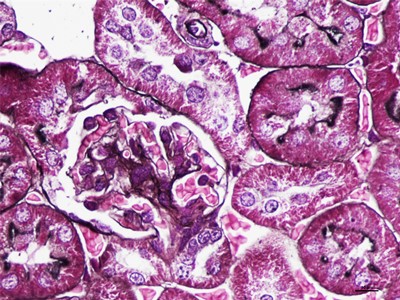

HE染色简称苏木精是是一种由碱性染液苏木精和酸性染液伊红构成的一种染色方法。是通显微镜下观察病理切片里病变的组织学形态变化来诊断疾病的,适用于胚胎学、病理学,生物医学,病理学教学与科研。HE染色对碱性染料和酸性染料亲和力都比较弱的现象称为中性。组织切片苏木素染色、分化与反蓝:将水化后的组织样本的切片使用PBS溶液浸泡清洗,每次浸泡5min,总共清洗3次。之后用移液枪吸取已经预先配置好的苏木素染色液,每个组织切片滴加100ul,充分染色10min。切片经HE染色后,要彻底脱水透明,才能用甘肃中性树胶封盖。he染色对于贴壁生长细胞,胰酶消化,调整细胞浓度约1×105/ml,滴加于盖玻片上(置于6孔板中),培养相应时间后,取出细胞爬片,用PBS 洗涤3次。着色情况与组织或细胞的种类有关。切片在苏木素染液中停留过长;或切片太厚;或分化时间太短。这种情况首先镜下看看切片厚度(最佳厚度1-2层细胞核),要么重新染色,要么重新制片。染色的最终结果是:细胞核呈蓝色、胞质、肌纤维、胶原纤维和红细胞呈深浅不一样的红色,病理技术服务提醒:在进行HE染色需要染色时间,脱水,染色时间不一样,需要等 ,明确HE评判标准。